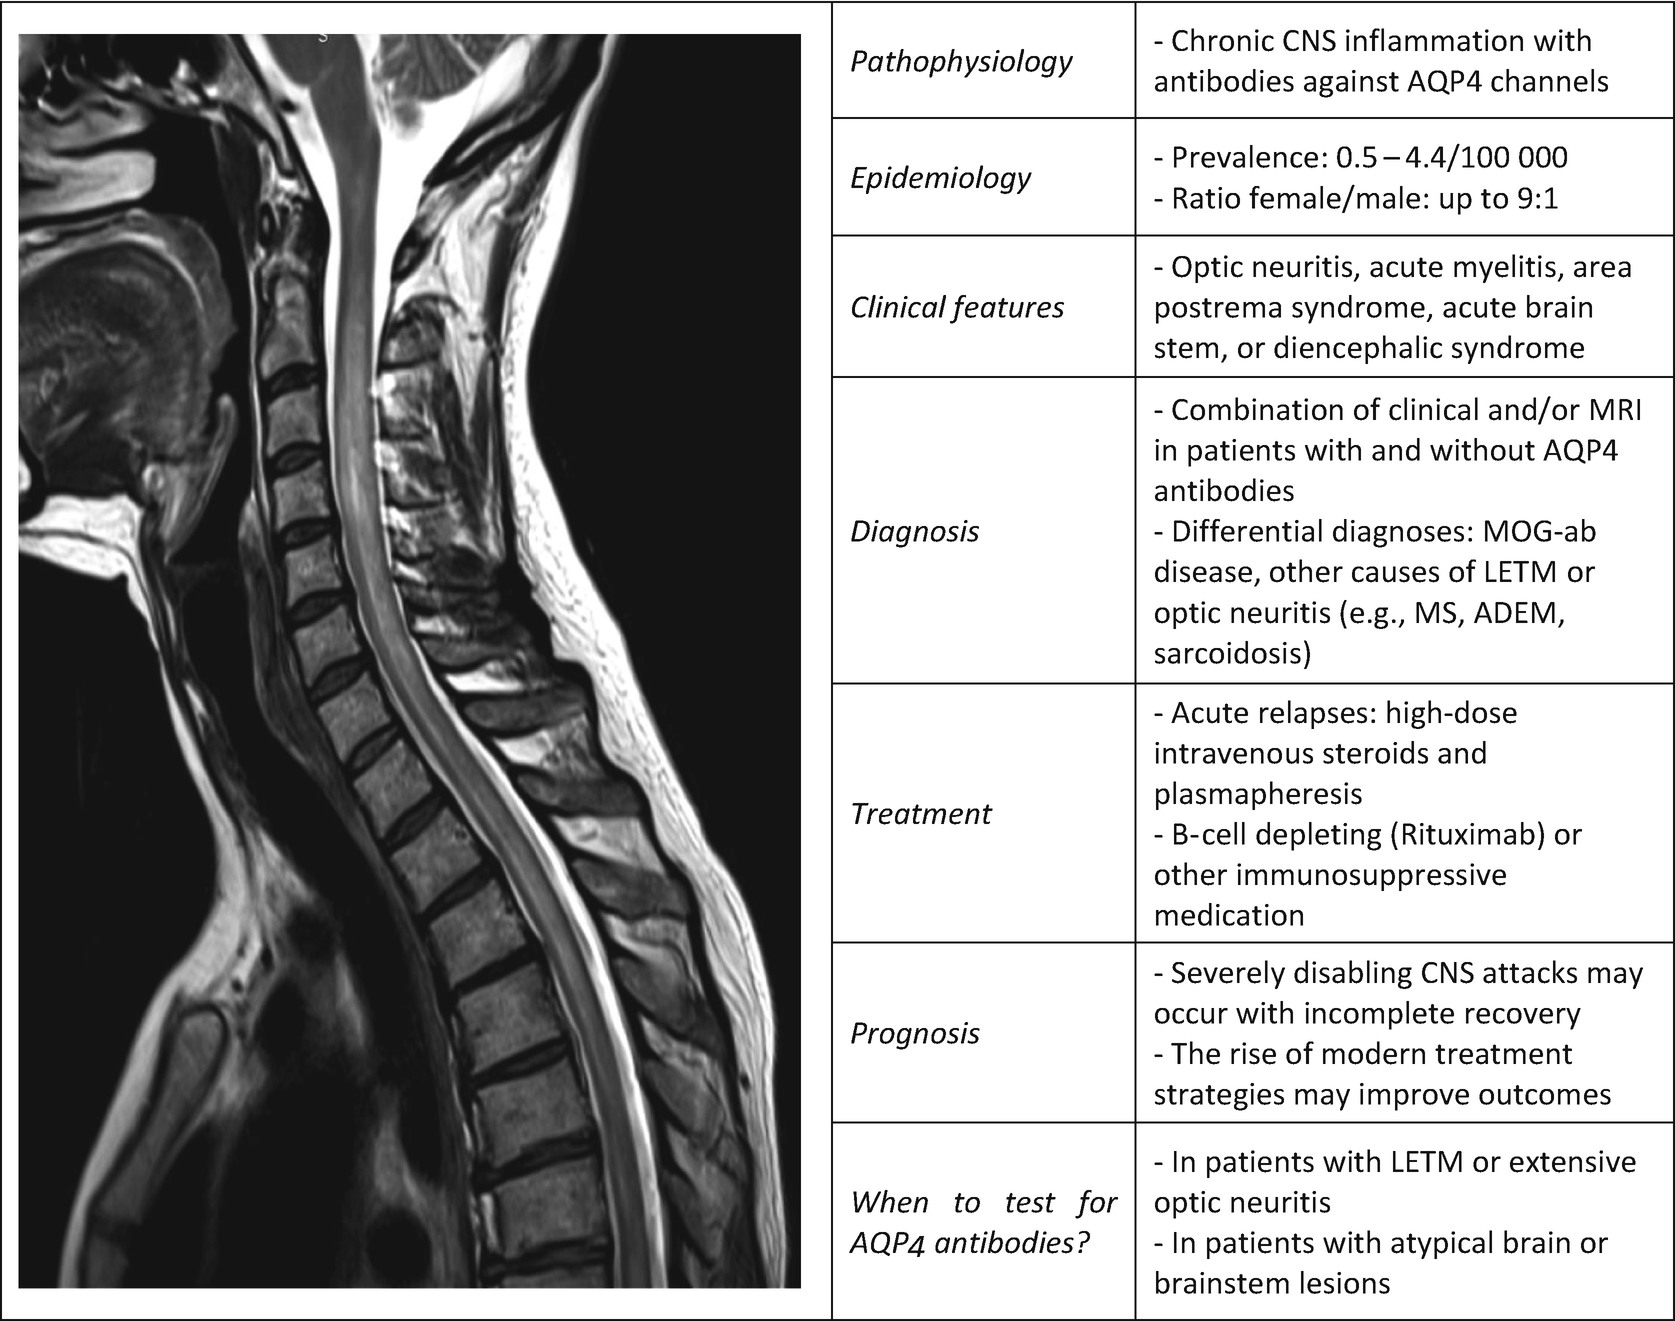

Devic’s neuromyelitis optica (NMO) or Devic’s disease is a severe idiopathic immunomediated inflammatory demyelinating and necrotizing disease that predominantly involves the optic nerves and spinal cord Recent immunopathological evidences suggest that the target antigen is aquaporin4, the dominant water channel in the central.

Syndrome de devic. Devic's neuromyelitis optica (NMO) associates optic neuritis and myelopathy without other neurological signs Many patients with NMO may be diagnosed as having multiple sclerosis (MS) However, there have been no previous studies comparing these two patho logies and it is still unclear if NMO is a separate entity or a subtype of MS. Definitions of Devic disease A syndrome characterized by acute OPTIC NEURITIS in combination with acute MYELITIS, TRANSVERSE Demyelinating and/or necrotizing lesions form in one or both optic nerves and in the spinal cord. Devic's syndrome Latest Articles Views & Reviews Worldwide incidence and prevalence of NMO A systematic review Viktoria Papp, Melinda Magyari, Orhan Aktas, et al Bruna Klein da Costa, Renata Brant de Souza Melo, Giordani Rodrigues dos Passos, et al Neurology September 09, Show more.

Devic's syndrome is a demyelinating disorder related to MS but with a different cause unknown at present It is also called neuromyelitis optica if you do not have optic nerve damage (and you would have after 23 years) you do not have Devic's Optic nerve damage can be identifies by opthalmoscopic examination or visual evoked potentials. Neuromyelitis optica spectrum disorder (NMOSD), Devic's disease, Devic's syndrome Specialty Neurology Symptoms Vision loss, sensory loss, weakness, bladder dysfunction Usual onset Median age 40 for AQP4IgG, age 31 for MOGIgG Types recurrent, monophasic Diagnostic method AntiAQP4 antibodies, MRI, and symptoms Differential diagnosis. Neuromyelitis optica (NMO), also known as Devic's disease, is a rare condition where the immune system damages the spinal cord and the nerves of the eyes (optic nerves) NMO can affect anyone at any age, but it's more common in women than men Symptoms of NMO Each person will experience different symptoms, which can range from mild to severe.

Neuromyelitis optica (NMO) and NMO Spectrum Disorder (NMOSD), also known as Devic's disease, is an autoimmune disorder in which white blood cells and antibodies primarily attack the optic nerves and the spinal cord, but may also attack the brain The damage to the optic nerves produces swelling and inflammation that cause pain and loss of vision;. Neuromyelitis optica (NMO) or Devic's syndrome is a severe demyelinating disease of the central nervous system involving preferentially the optic nerves and the spinal cord. Devic's neuromyelitis optica (NMO) associates optic neuritis and myelopathy without other neurological signs Many patients with NMO may be diagnosed as having multiple sclerosis (MS) However, there have been no previous studies comparing these two patho logies and it is still unclear if NMO is a separate entity or a subtype of MS.

Neuromyelitis optica (also known as Devic's disease) is an idiopathic, severe, demyelinating disease of the central nervous system that preferentially affects the optic nerve and spinal cord Neuromyelitis optica has a worldwide distribution, poor prognosis, and has long been thought of as a variant of multiple sclerosis;. A case of classic neuromyelitis optica (Devic’s syndrome) triggered by pegylatedinterferon αpdf even though its si de effects are so metimes un predictab le and severe. Neuromyelitis optica – Devic’s syndrome, update Antibody to aquaporin4 in the longterm course of neuromyelitis optica Mult Scler, deivc, pp Antiaquaporin4 AQ4 antibodies are a specific biomarker of the entity and, since their discovery, both the number of symptoms and the radiological data about the disease have progressively increased, and the concept of clinical spectrum of NMO.

Neuromyelitis optica spectrum disorder (NMOSD), also known as Devic disease, is a chronic disorder of the brain and spinal cord dominated by inflammation of the optic nerve (optic neuritis) and inflammation of the spinal cord (myelitis) Classically, it was felt to be a monophasic illness, consisting of episodes of inflammation of one or both optic nerves and the spinal cord over a short period of time (days or weeks) but, after the initial episode, no recurrence. Devic, syndrome (Neuromyelitis Optica) Rare 19/100,000, more frequent in girls and women (3 1) Central nervous system demyelinating inflammatory disease combining acute optic neuritis and acute myelitis due to the presence of antiaquaporin 4 antibodies For a long time regarded as a particular form of multiple sclerosis. Devic's syndrome is a demyelinating disease of the spinal cord and optic nerves It tends to have a poor prognosis, probably due to the occurrence of necrosis within lesions There is no proven effective treatment although relapses are commonly treated with corticosteroids and people with recurrent attacks may be managed with chronic immune.

Neuromyelitis optica (NMO) or Devic's syndrome is a severe demyelinating disease of the central nervous system involving preferentially the optic nerves and the spinal cord Until recently, NMO was described as an atypical multiple sclerosis IMS), characterized by an unusual clinical presentation, a severe relapsing progression, and a poor response to usual MS treatments. Neuromyelitis optica spectrum disorders (NMOSD) is an etiologically heterogeneous syndrome predominantly characterized by acute inflammation of the optic nerve (optic neuritis, ON) and the spinal cord () Episodes of ON and myelitis can be simultaneous or successive A relapsing disease course is common, especially in untreated patients. Neuromyelitis optica is an autoimmune disorder that affects the nerves of the eyes and the central nervous system, which includes the brain and spinal cord Explore symptoms, inheritance, genetics of this condition.